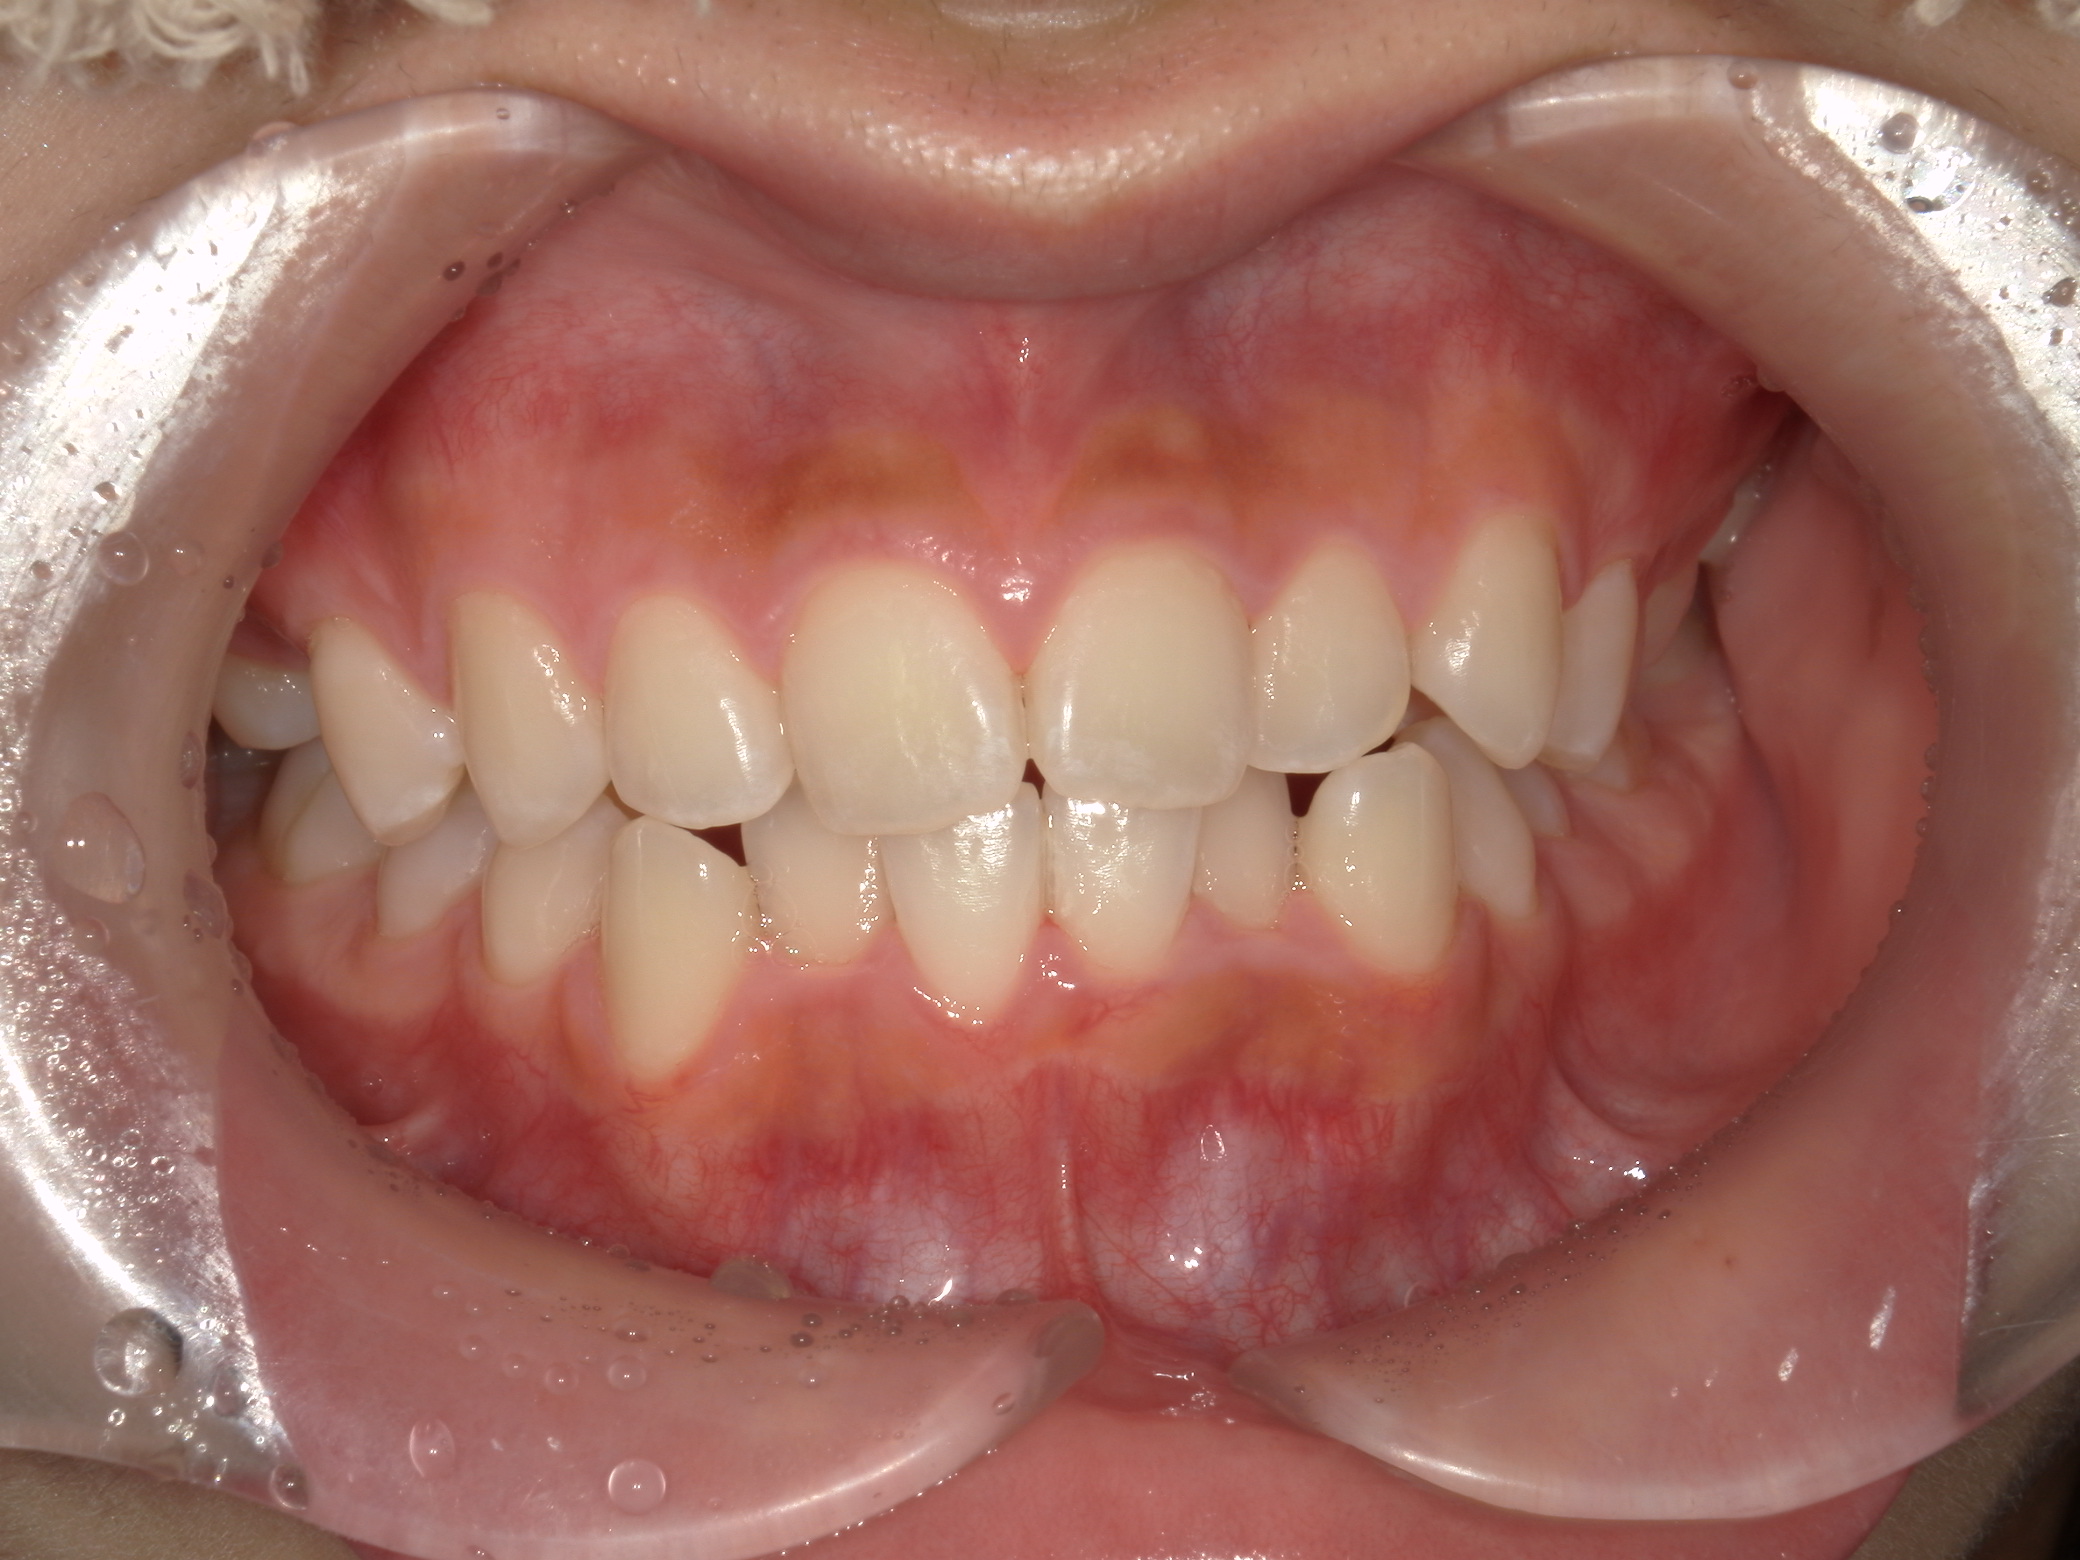

お口の中全体の写真

Before

| 患者の症状 | 下の前歯のガタツキが特に気になるということで矯正治療の相談をされた方です。 下の前歯以外にも上の歯列にもガタツキを認め、咬合の不均一もございました。 |

| 治療結果 | 上下とも歯列のガタツキは改善され、咬合関係も良好となりました。 |